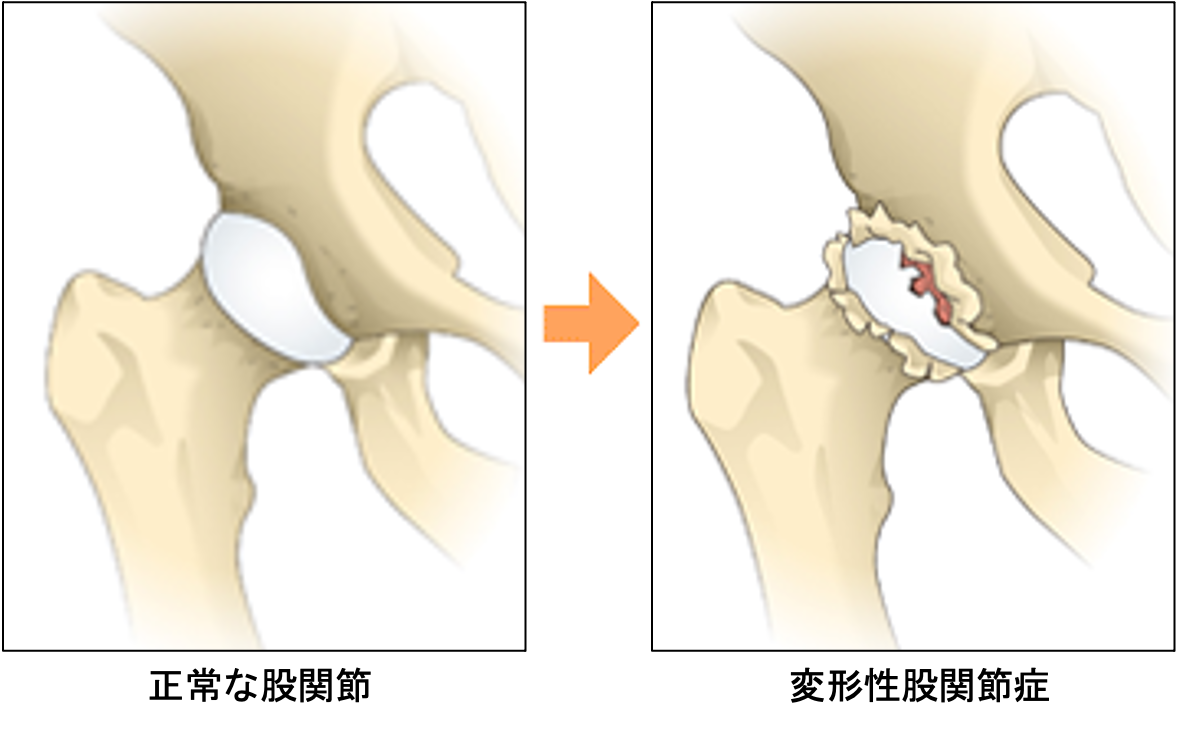

股関節は骨盤と大腿骨をつなぐ関節で、骨盤側のお碗状の受け皿となる「寛骨臼」に、球形の「大腿骨頭」がはまりこんでできている球関節です。下肢と胴体をつなぐ部分で歩行に非常に大切な関節です。表面は軟骨で覆われ、股関節にかかる力を吸収するとともに、関節の動きを滑らかにしています。さらに股関節は「関節包」という袋に包まれ、その中にある「関節液」が潤滑油の働きをしています。周囲は筋肉や靭帯で覆われており、これらの組織が股関節を支え、安定した動きをもたらします。股関節には歩行時には体重の3倍、立ち上がりやでは体重の6~7倍の力がかかると言われています。

股関節の軟骨がすり減ることで痛みが生じる病気で圧倒的に女性に多いのが特徴です。骨の形の異常から二次的に発症するものがほとんどで、幼少期の股関節発育不全(臼蓋形成不全)のために骨盤側の受け皿の部分が浅いことが原因です。

一般的な症状は足の付け根の痛み、違和感や動きの制限、ひきずり足歩行(跛行)ですが、お尻や膝の痛みなどを生じ、他の疾患と間違われることもあります。進行すると変形した側の脚(あし)が短くなり、左右の脚の長さが違ってくることもあり、階段の上り下りや、爪切り、正座ができないなど次第に日常生活に支障をきたすようになります。まずは日常生活指導、運動療法、薬物療法などの保存療法を行いますが、股関節症の状態によっては早期の手術が必要となることがあります。